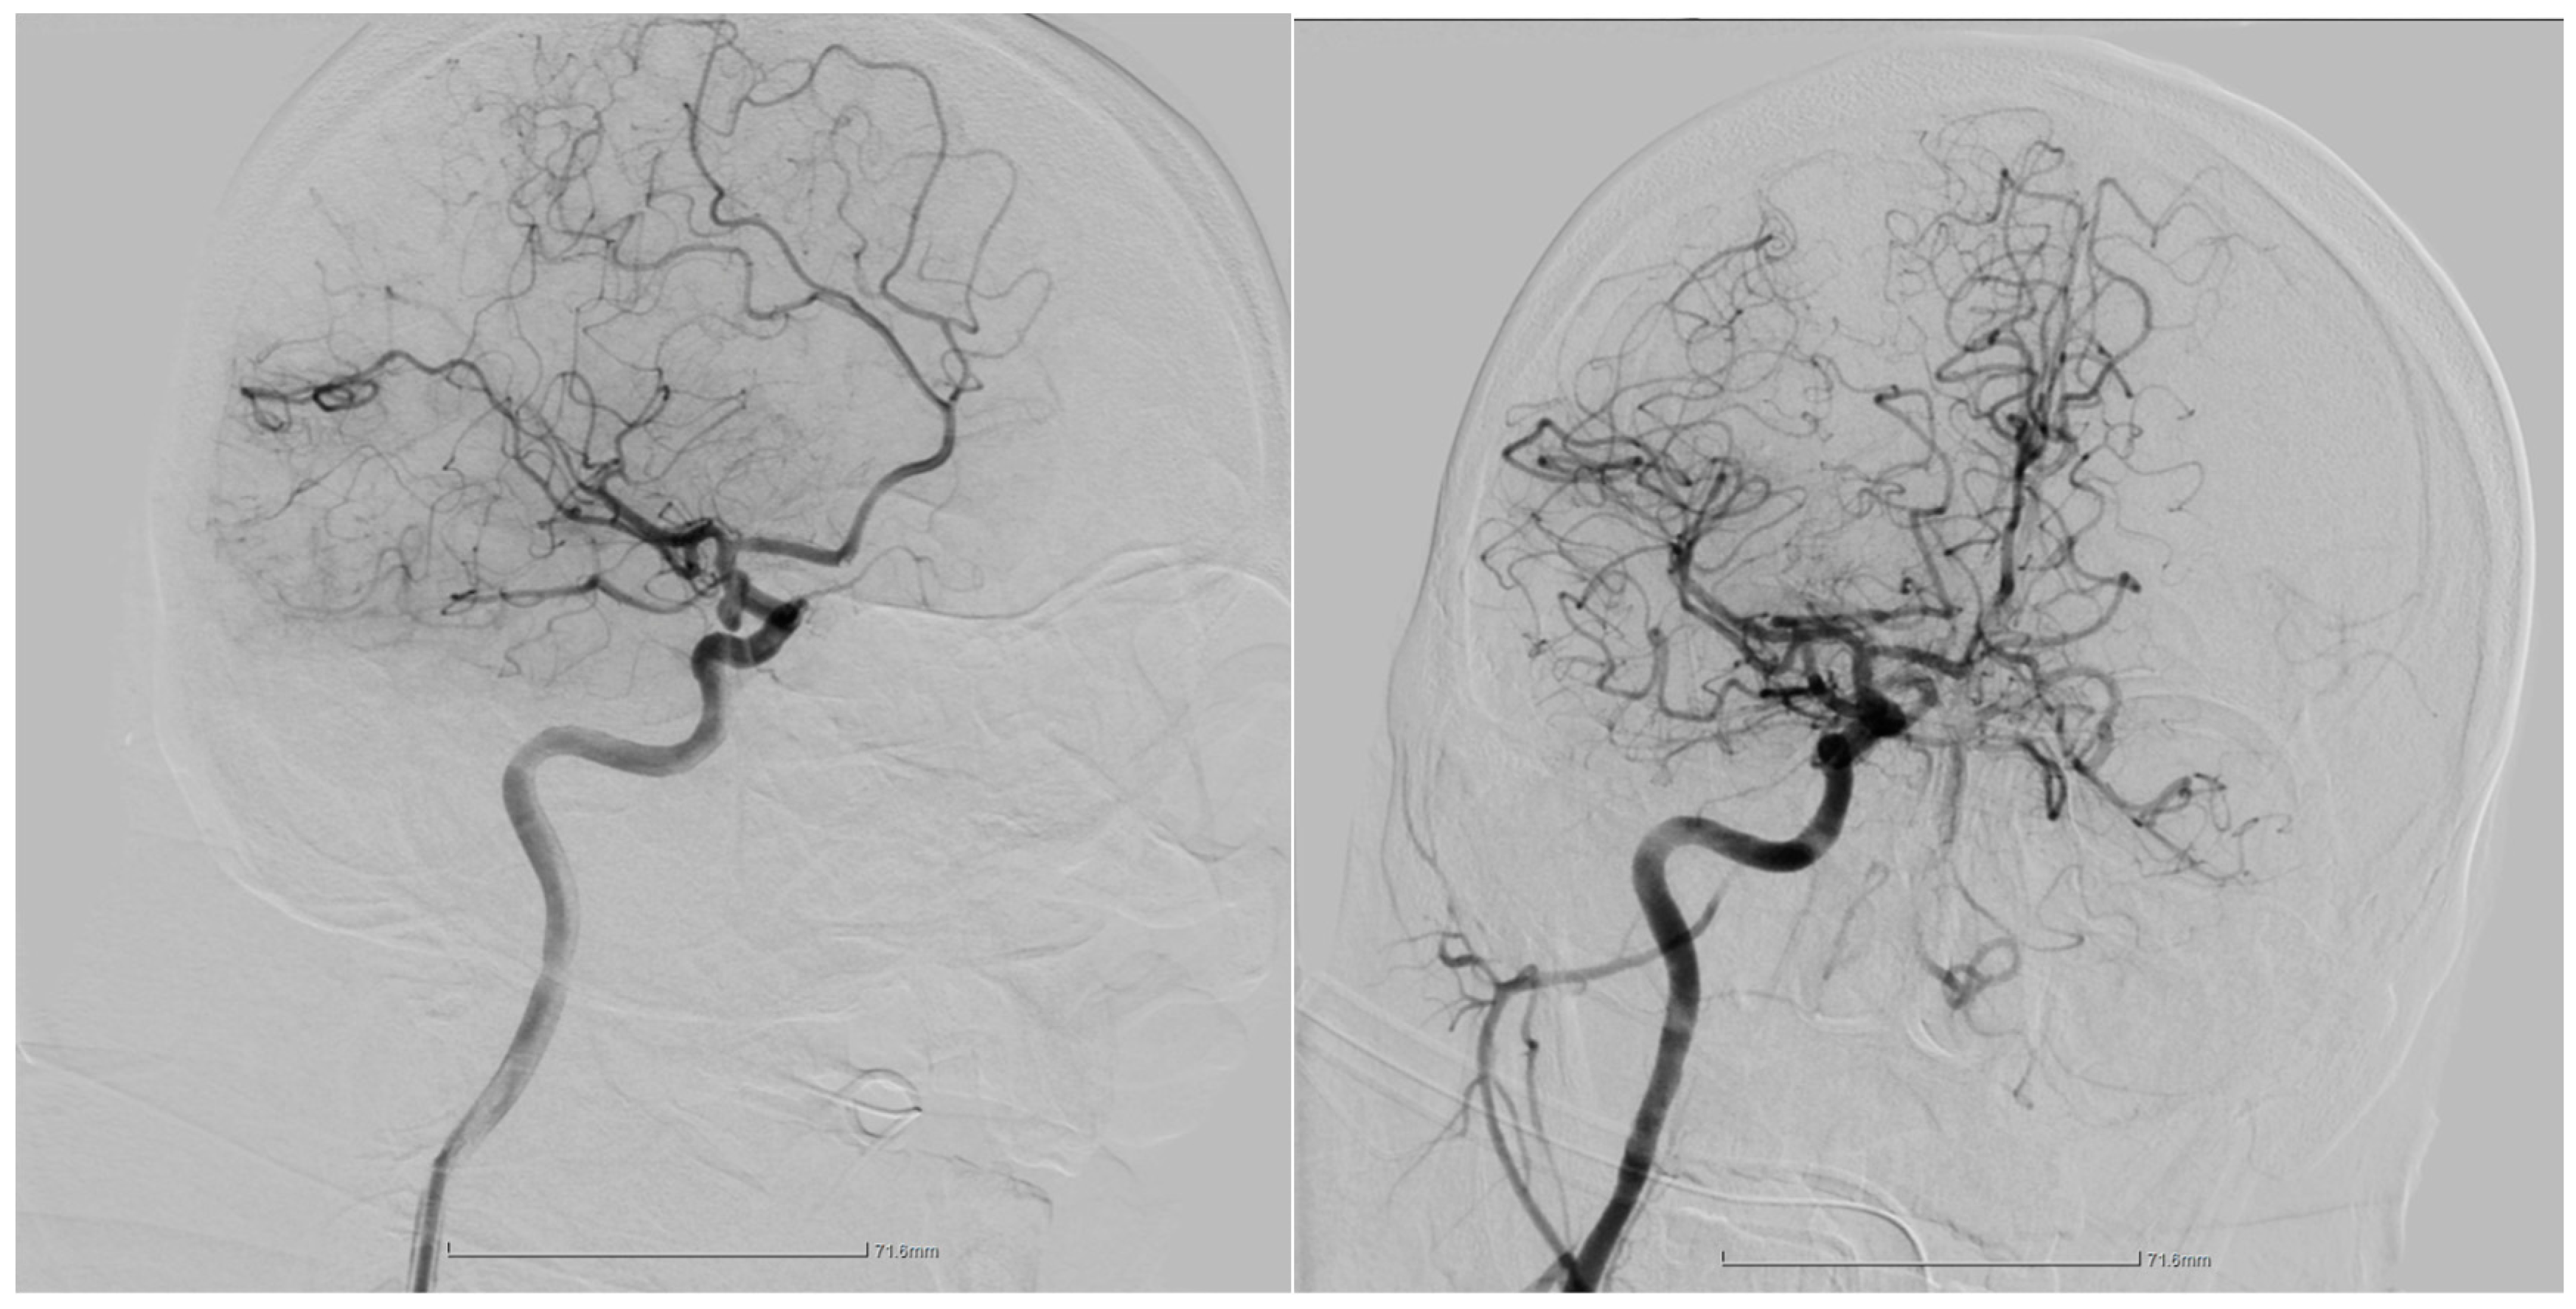

2.1. Case Presentation